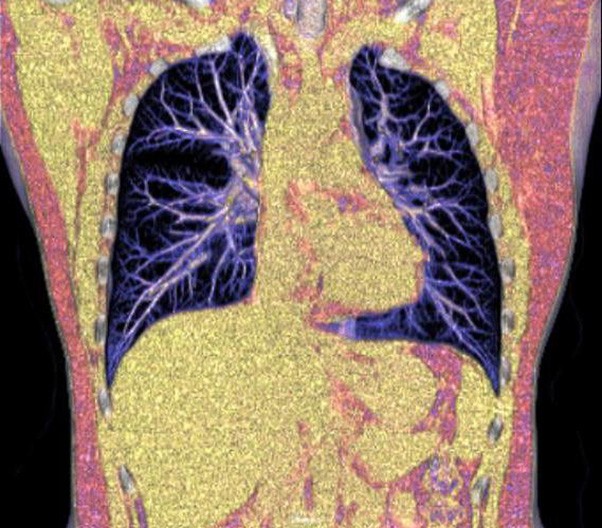

Lung reverse scanning eliminate respiratory motion artifact

NDI NanoDose Iteration Algorithm (NDI) is an innovative iterative technique for image reconstruction that takes full advantage of deep learning in anatomical structure in image space as well as model-driven iteration involving tube and detector in projection space, with the aim to generate sharp and high-resolution images at the lowest possible dose.